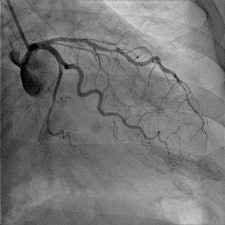

The main advantage for patients is a 50% reduction in total radiation dose through postprocessing of the images obtained by the flat-panel detectors. For one standard adult coronary angiogram, the typical dose used to be 6 to 7 mSv. Cardiologists at the Ghent lab are hoping they will be able to achieve 2 to 3 mSv.

"The quality and innovation of the four main cath lab companies -- Siemens, Phillips, GE, and Toshiba -- are very close, but in our case we chose the Phillips AlluraClarity system due to its radiation dose reduction capabilities," Taeymans said.